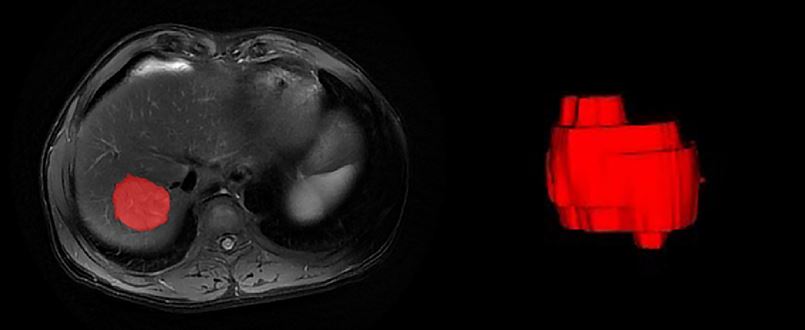

Based on a large cohort, this study highlights how the grade of HCC can be approached with radiomics analysis of MRI images.

Article: Predicting the grade of hepatocellular carcinoma based on non-contrast-enhanced MRI radiomics signature